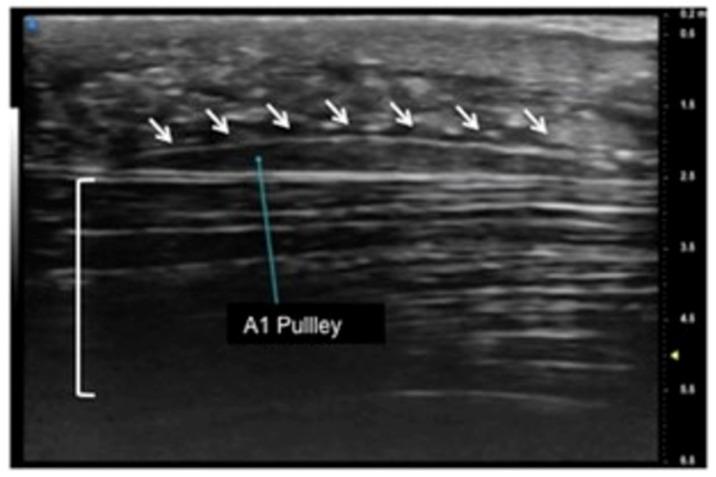

Musculoskeletal ultrasound involves the study of many superficial targets, especially in the hands, wrists, and feet. Many of these areas are within the first 3 cm of the skin surface and are ideal targets for ultra-high-frequency ultrasound. The high spatial resolution and the superb image quality achievable allow foreseeing a wider use of this novel technique, which has the potential to bring innovation to diagnostic imaging.

肌肉骨骼超声涉及对许多浅表目标的研究,尤其是在手部、腕部和足部。这些区域中的许多都位于皮肤表面的前3厘米内,是超高频率超声的理想目标。可实现的高空间分辨率和卓越的图像质量使得有望更广泛地使用这种新技术,它有可能给诊断成像带来创新。